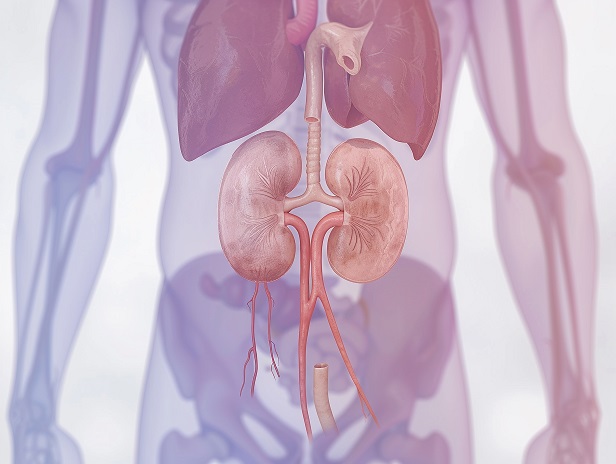

Тайлер Кристина Георгиевна врач терапевт- нефролог с 11-ти летнем стажем, имеющий опыт работы в стационаре, поликлинике и центре трансплантологии. Специализируется на диагностике и лечении заболеваний внутренних органов, в том числе у коморбидных пациентов с заболеваниями почек с кардиальной, эндокринной или системной патологиями. Ведение пациентов с острыми хроническими патологиями.

Приоритетная зона интересов — пациенты с патологией почек. Специализируется на ведении пациентов с хронической болезнью почек, нефритами, , нарушениями водно-электролитного баланса и артериальной гипертензии «почечного» характера.

Владеет навыками интерпритации расширенных лабораторных анализов(биохимия, иммунология, коагуллограма). Оценка данных УЗИ, КТ, МРТ почек. Определение показаний к заместительной почечной терапии методом диализа или трансплантации.